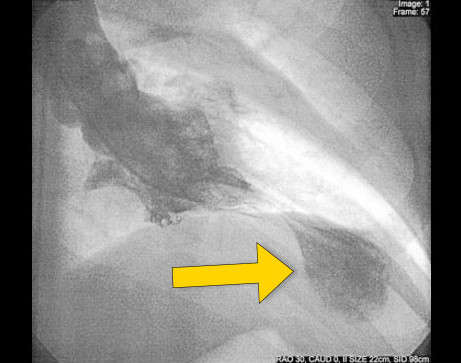

TCM的实际发生率尚不清楚,但该病可能占所有疑似急性心肌梗死病例的1%~2%。TCM患者一般表现为胸痛、心电图ST段抬高和心肌酶水平升高,与急性MI的表现是一致的。但当患者行冠状动脉血管造影术时,可发现无显著冠状动脉狭窄(如图所示),而左心室造影显示左心室心尖部存在球样扩张。

收缩期左心室造影显示特性心尖部球样扩张伴心尖室壁运动缺失(箭头)。